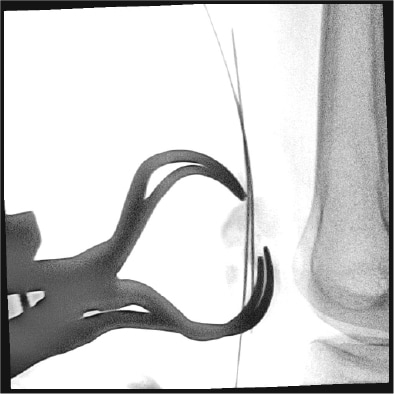

整形外科的処置等で金属インプラントを使用する患者様に対して、Philips MetalSmartソフトウェアが自動的に視野内の金属オブジェクトに起因する過度なX線量の増加を防ぐことにより、メタルアーチフェクト(ハレーション)を抑え適切な画質を提供します。